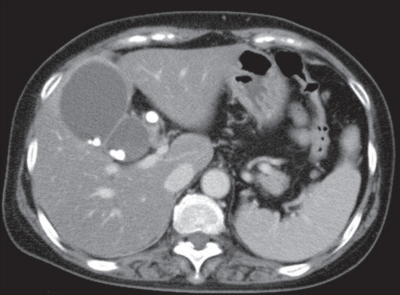

血液所見:赤血球448万、Hb 13.8g/dL、Ht 37%、白血球15,800、血小板28万。血液生化学所見:総ビリルビン0.9mg/dL、AST 28U/L、ALT 18U/L。CRP 9.8mg/dL。腹部造影CTを別に示す。